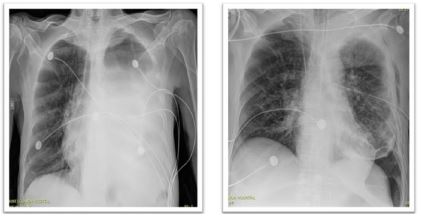

The patient was transferred to the ICU post-Operative. Extubated day one post-Operative, hemodynamically stable with 5 L O2 NC requirements (Figure 3). Diet resumed on day two post-Operative. Intra-Operative cultures returned positive for Ecoli ampC and targeted anti-biotherapy started. During his stay patient presented multiple respiratory complications that required a new chest tube placement, bronchoscopy, CT guided drainage of a left pleural effusion.

Figure 3: Chest X-ray pre-OP vs day 1 post-Op.